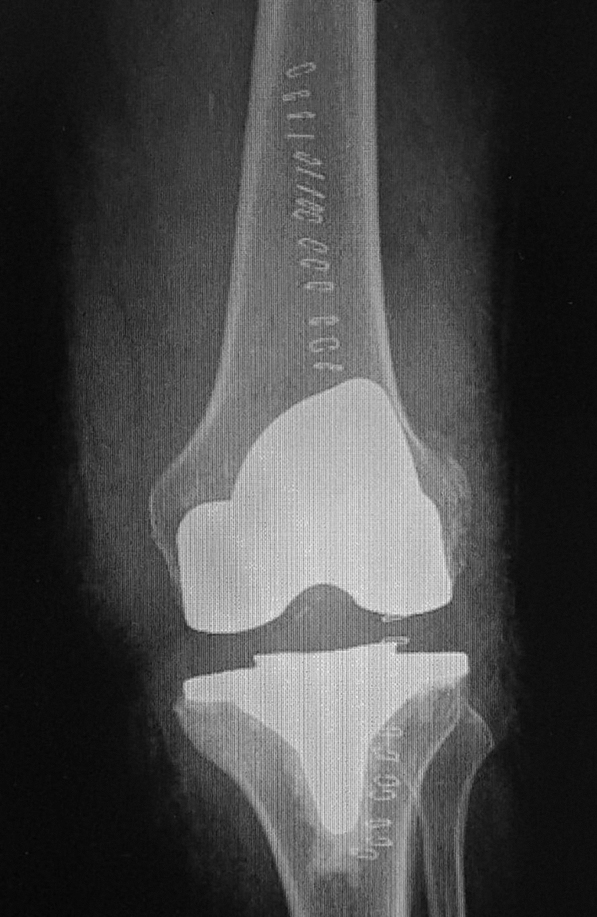

Iz lične foto-dokumentacije doc. dr Barjaktarovića: Primarna artroplastika levog kolena-attune |

Operacije zamene kolena takođe je najučestalija kod pacijenata starije životne dobi, zbog oštećenja izazvanih degenerativnim promenama i upalnim procesima/oboljenjima. Osim toga što može da bude totalna ili parcijalna, raspolaže velikim brojem operativnih tehnika i različitim tipovima endoproteza. Standardna totalna artroplastika kolena podrazumeva dva osnovna pristupa: kod manjih oštećenja zgloba, takozvana CR (cruciate retaining) procedura jeste da se žrtvuje prednji ukršteni ligament, a da se zadnji sačuva, dok se u težim slučajevima primenjuje PS (posterior stabilized) postupak koji predviđa da se žrtvuju oba ligamenta, a implantira endoproteza koja je za to posebno dizajnirana. Uz preoperativnu pripremu kao i za operacije zamene kuka, artroplastika kolena se izvodi u opštoj ili spinalnoj anesteziji, i u dobrim uslovima uobičajeno traje oko jedan sat.